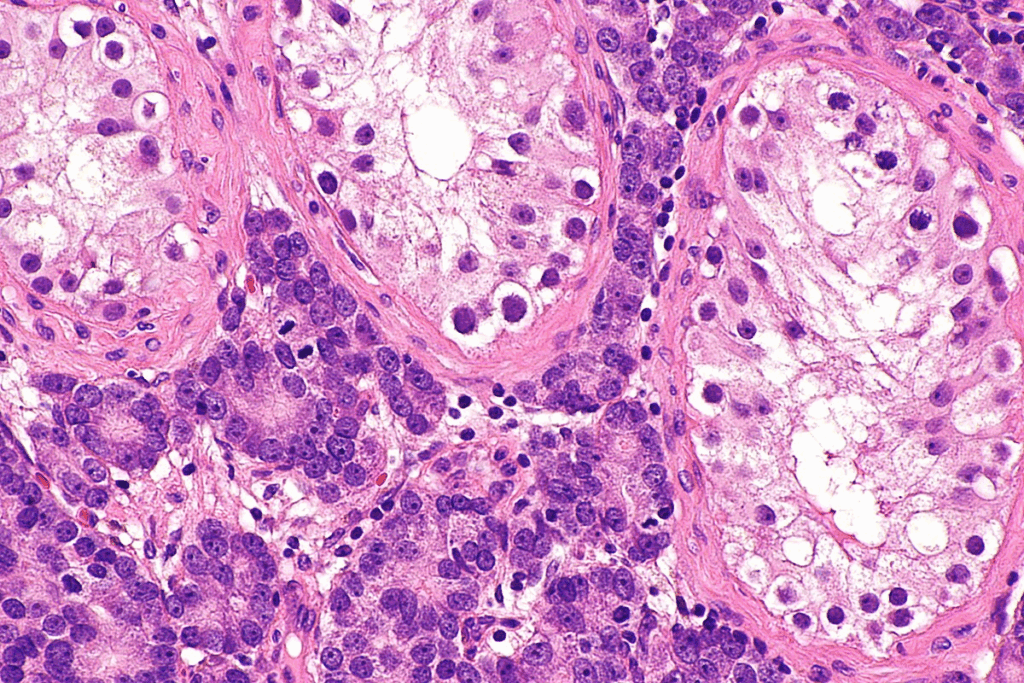

The main cause of UTIs is Escherichia coli (E. coli) bacteria. It’s found in the gut. E. coli can easily move to the urinary tract and cause infection. Other bacteria can also lead to UTIs, but E. coli is the most common.

It’s key to know the difference between UTIs and STIs. They have different causes and treatments. UTIs are mainly caused by bacterial infections, like E. coli. STIs, on the other hand, are caused by specific pathogens, such as Chlamydia trachomatis or Neisseria gonorrhoeae.

The science of bacterial transfer during sex is complex. Research shows that bacteria can move through skin contact. Some bacteria, like E. coli, are more likely to cause UTIs because they stick well to the urinary tract walls.

E. coli causes about 80% of simple UTIs. It’s usually in the gut but can move to the urinary tract during sex, including oral sex.

E. coli in the urinary tract can cause infection, more so in women with shorter urethras. Knowing how E. coli leads to UTIs is key for prevention and treatment.